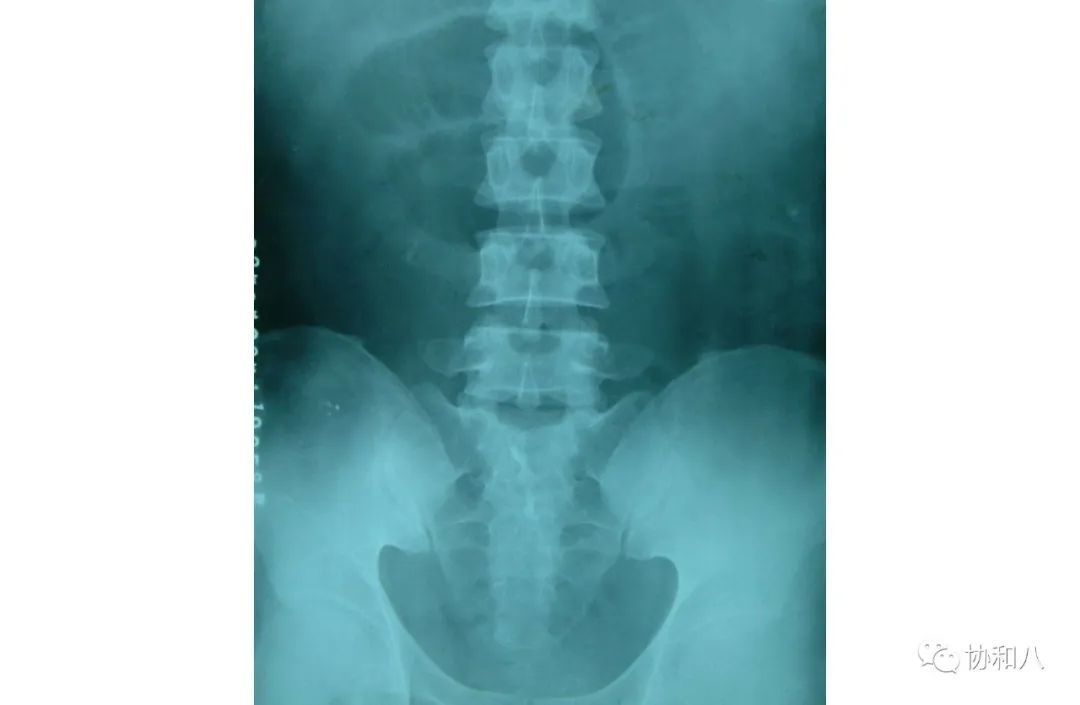

5. 咖啡豆征 Coffee bean sign:

不完全性绞窄性肠梗阻时,气体可以通过近端梗阻点进入,却不能排出,以致闭襻肠曲明显扩大,闭襻肠曲的内壁因水肿而增厚且相互靠扰,形成一条致密线状影,形似咖啡豆。